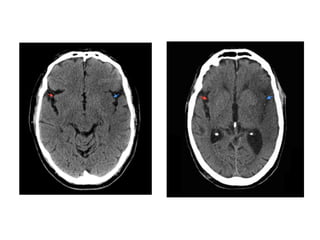

c) Hyperdense artery :

-Represents acute thrombus within the vessel

-Most commonly recognized with basilar and

proximal MCA thrombosis

-False positives can occur if a vessel is partially

calcified or if the haematocrit is raised (i.e.

polycythaemia)

-On the left a patient with a dense MCA sign

-On CTA : occlusion of the MCA is visible